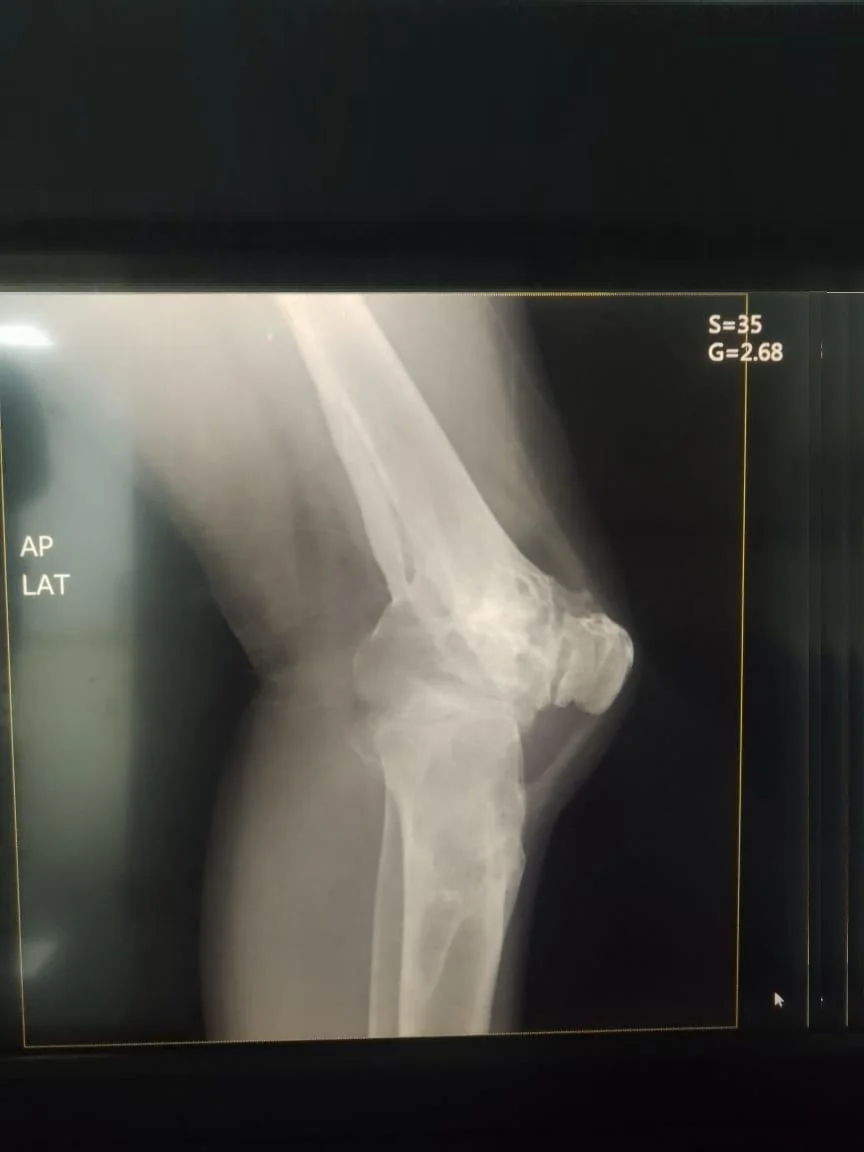

Antes Radiografía preoperatoria de fractura de tibia y osteoartrosis de rodilla

Traumatología

Reemplazo articular

Fractura de Tibia

• Perfil del Paciente: Masculino, 50 años.

• Historia Clínica: Antecedentes de 25 años de evolución con dolor crónico y pérdida de movilidad.

• Diagnóstico: Osteoartrosis secundaria a fractura de rodilla antigua.

• Resultado (Caso 2024): Intervención exitosa con recuperación completa. Actualmente el paciente presenta una evolución óptima y retorno a su vida cotidiana.